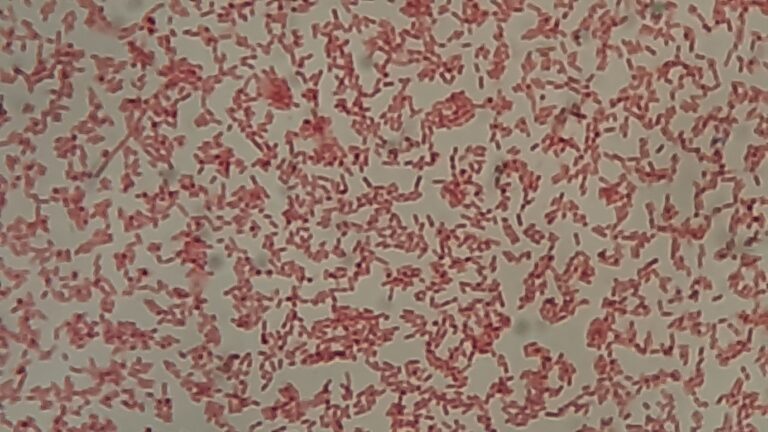

Gram Negative Rods of Citrobacter koseri - YouTube

Citrobacter koseri, formerly known as Citrobacter diversus, is a Gram ...

Based on this image's title: “Citrobacter koseri”